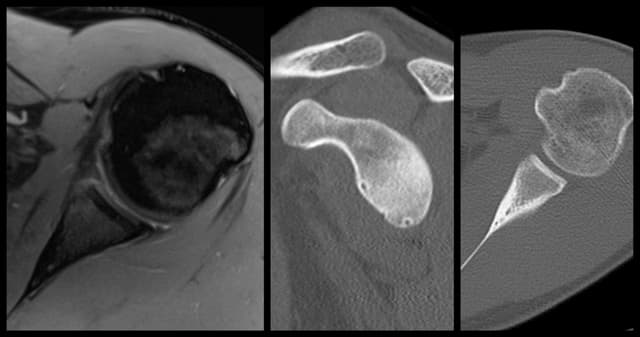

Latarjet Procedure